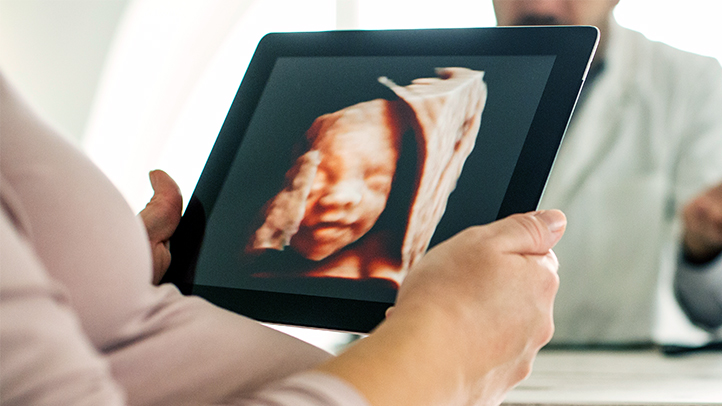

Siêu âm 4D là một kỹ thuật siêu âm hiện đại sử dụng sóng âm để tạo ra hình ảnh chuyển động 3D hoặc 4D của thai nhi. Kỹ thuật này có nhiều lợi thế vượt trội so với siêu âm 2D và 3D, mang đến cho mẹ bầu những trải nghiệm thú vị khi nhìn thấy con yêu một cách rõ nét và chân thực.

Siêu âm 4D là phương pháp hữu hiệu giúp bác sĩ đánh giá tình trạng và quan sát sự phát triển của thai nhi. Phương pháp này cung cấp hình ảnh rõ nét và chân thực về thai nhi, giúp bác sĩ phát hiện sớm các bất thường và theo dõi sự phát triển của thai nhi một cách toàn diện.